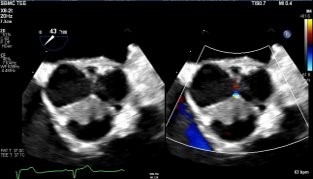

A 55-year-old male with well-controlled HIV presented with acute febrile illness, executive dysfunction, and visuo-cerebellar deficits. Initial concerns included meningoencephalitis, CNS lymphoma, and progressive multifocal leukoencephalopathy. Extensive infectious workup was unrevealing. Brain MRI revealed numerous bilateral hyperintense lesions. CT chest/abdomen identified bilateral axillary adenopathy, right pulmonary embolus, and splenic infarcts. Arterial Doppler showed a right tibial artery occlusion. Transthoracic echocardiography demonstrated aortic valve vegetations. Despite multiple embolic events, all blood cultures remained sterile, raising concern for blood culture–negative endocarditis, malignancy-associated endocarditis, and autoimmune etiologies. This prompted further serological testing for C. burnetti, B. henselae, Brucella and tumor markers, all of which were unremarkable.

Autoimmune evaluation revealed ANA >1:1280, anti-dsDNA positivity, and low complement levels, meeting the 2019 American College of Rheumatology criteria for SLE (12 points). Transesophageal echocardiography confirmed multiple echogenic densities on the aortic valve, consistent with a diagnosis of LSE in the setting of newly diagnosed SLE. LVEF was moderately reduced (35–40%) with global hypokinesis. The patient was started on therapeutic anticoagulation and guideline-directed therapy for heart failure, with rheumatology consulted for long-term treatment.